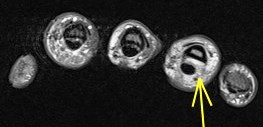

Annular pulley tears result in bowstringing of the tendon. Compare the sagittals of the 4th finger with the sagittal of the 5th finger which is not bowstrung (5th is labeled). I dont believe I have recognized only half of the pulley torn before.

Ulnar aspect A3 pulley tear with bowstringing of the flexor tendons